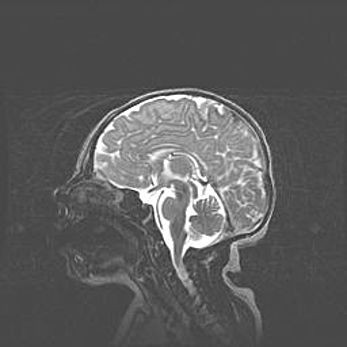

Церебральная ишемия II.

Возраст: 7 дней

Вес: 3350 г

Пол: женский

Окружность головы: 35 см

Срок гестации: 39 недель

Ишемия головного мозга – это состояние, которое развивается в ответ на кислородное голодание вследствие недостаточного мозгового кровообращения. У новорожденных она является следствием дефицита кислорода, что ведет к метаболическим расстройствам различной степени тяжести в тканях головного мозга, в том числе к развитию коагуляционных некрозов и гибели нейронов.